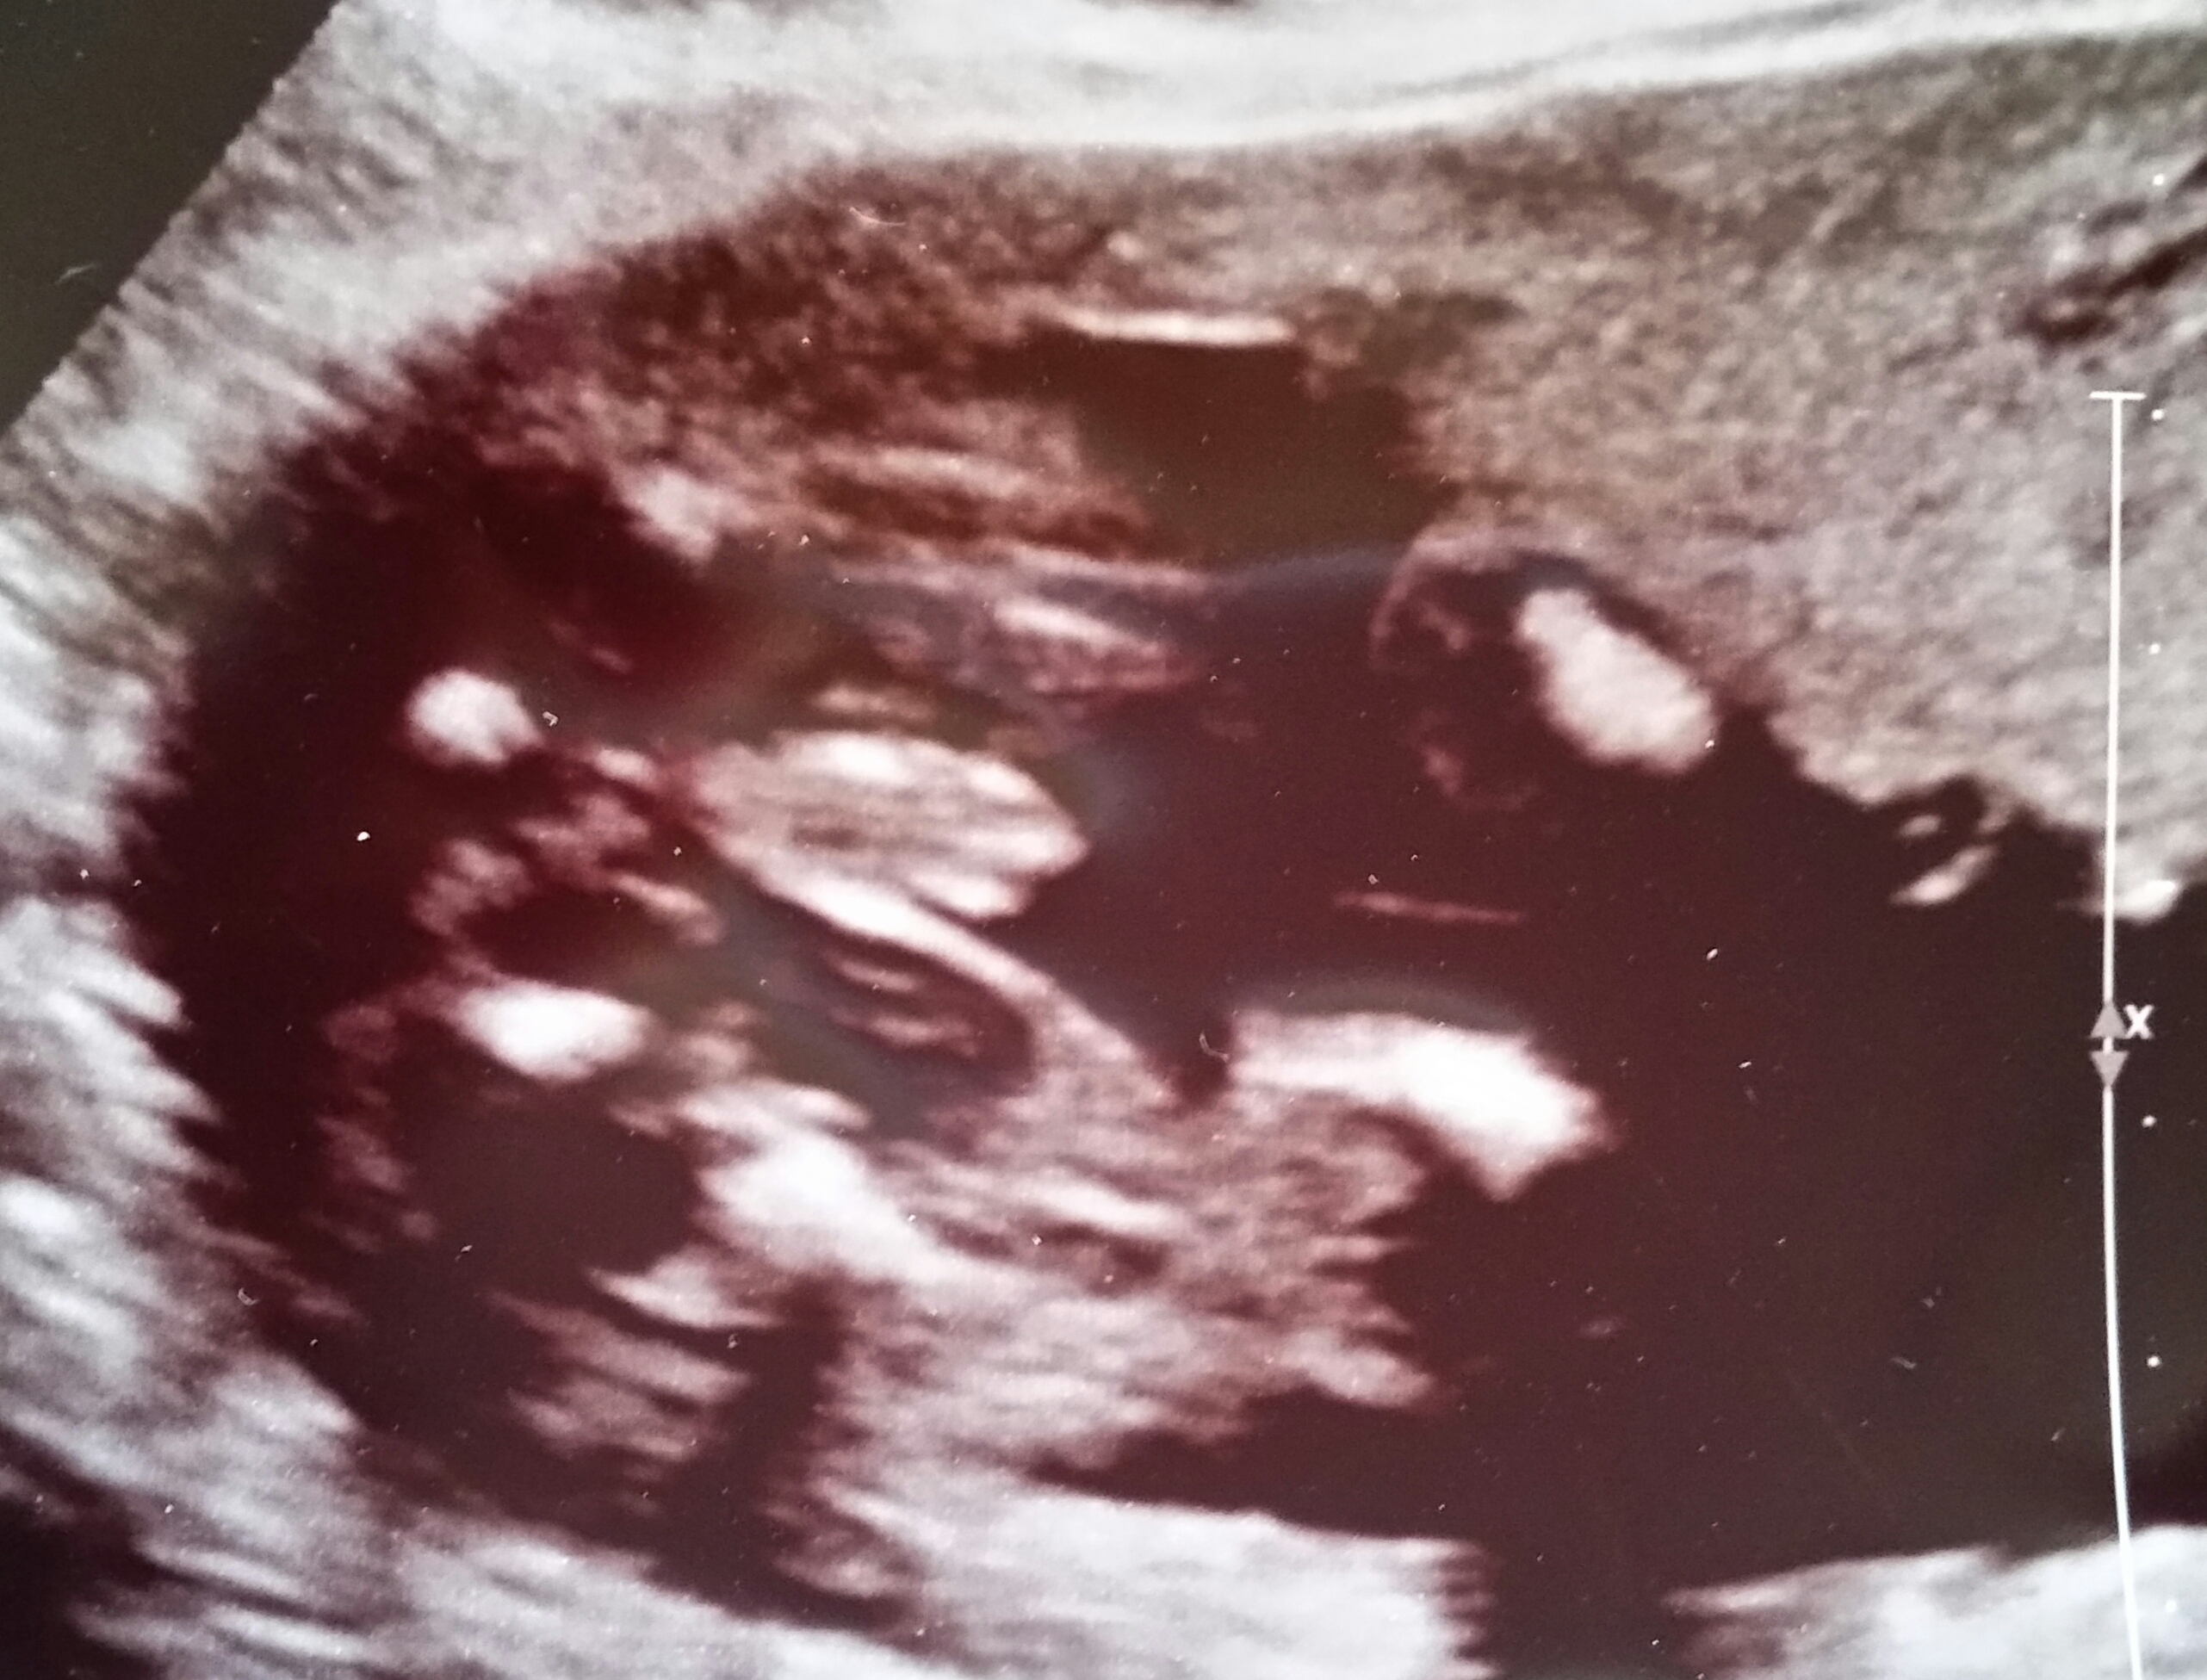

Hey all you mama's of girls I'm a mama of boys and I'm really hoping maybe you all would know if there is any hope of this ultrasound picture being swollen girlie parts and not tiny boy parts. I feel that this baby is a girl but tech said 100% boy, I don't see it. She gave me the best shot she could get and it looks nothing like my other two boys. Please give me some good honest advice even if it's not what I really want to hear I need to hear it. Attachment 26385Attachment 26386Attachment 26387